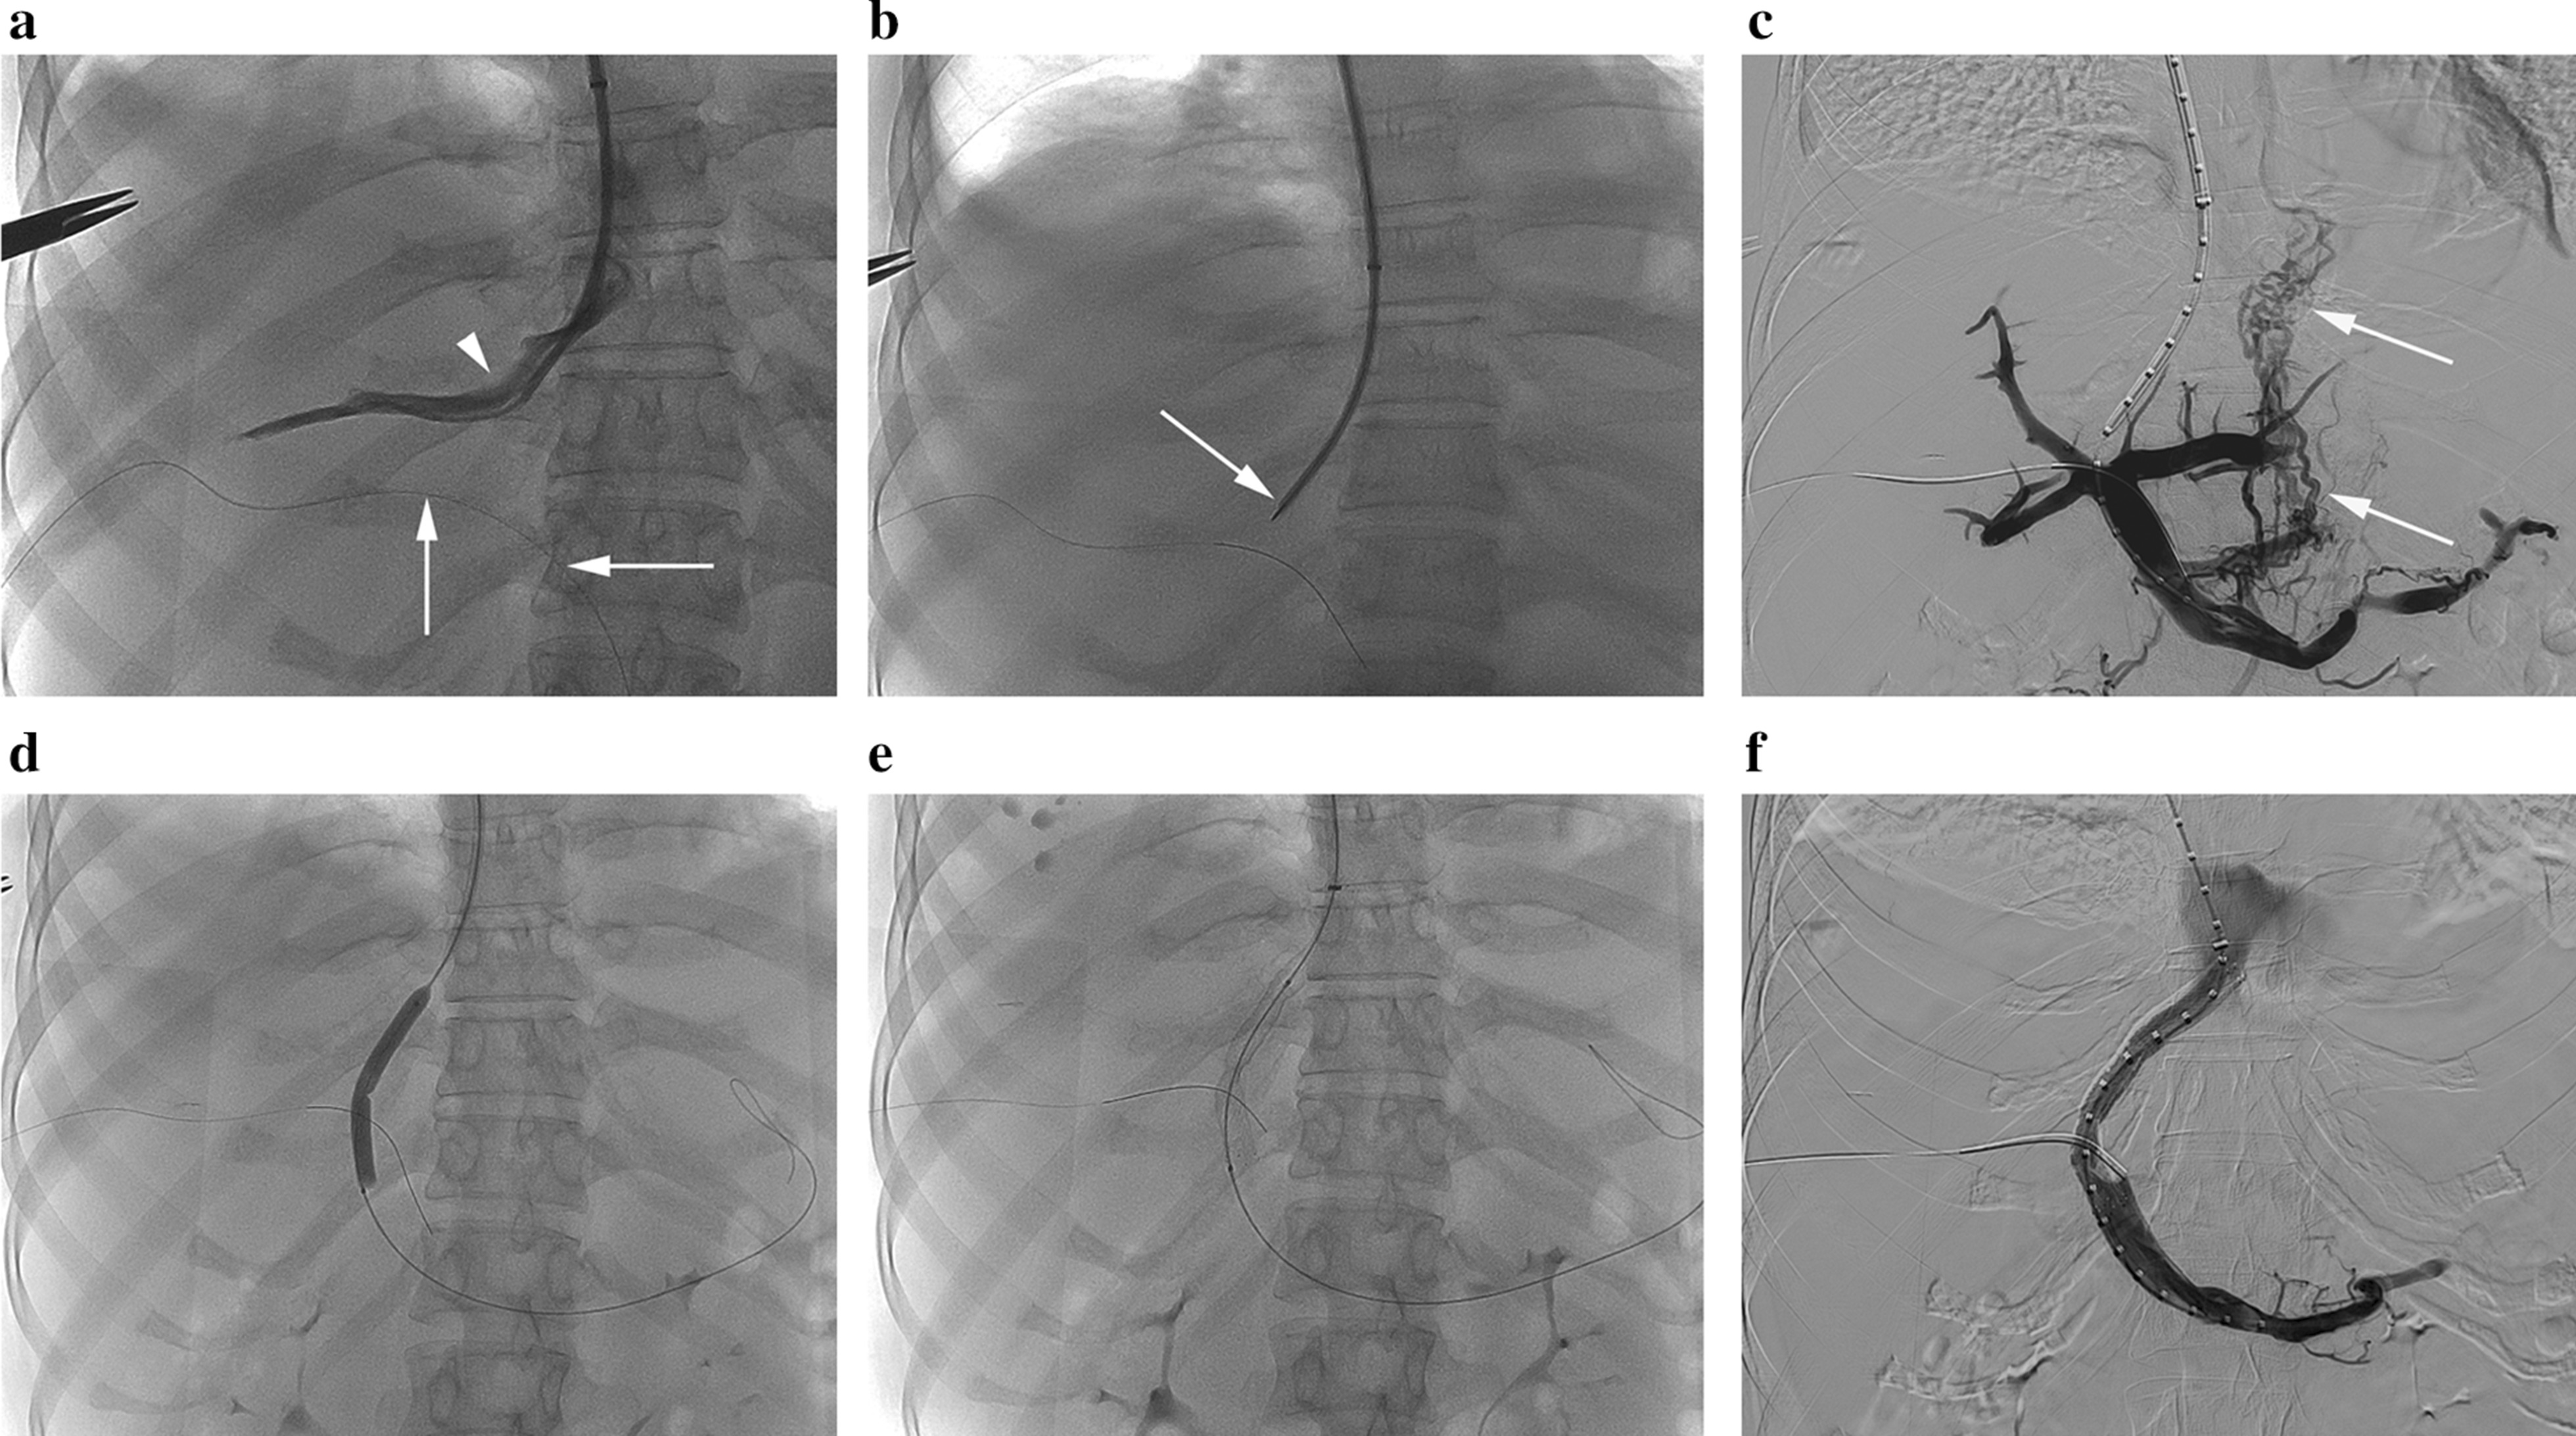

The TIPS procedure was performed under the guidance of ultrasound and digital subtraction angiography (Artis Zee Celling, Siemens Medical Solutions, Muenchen, Germany). In summary, venous access was attained through the right internal jugular vein, then afterwards the right or middle hepatic vein was catheterized. A standard Rösch-Uchida TIPS set (Cook Medical, Bloomington, IN, US) was used to create a parenchymal tract between the hepatic vein and the intrahepatic portion of the portal vein. In some patients in whom access to the portal vein by transhepatic puncture proved difficult, percutaneous insertion of a 0.014-in wire into the portal system would be used to provide access. After measurement of pressures in the portal vein and the right atrium, the tract was dilated with balloon catheters, and then a bare stent (Bard E-Luminexx® Vascular Stent, C. R. Bard, Inc, Karlsruhe, Germany) followed by a stent-graft (Viabahn, W. L. Gore & Associates, Inc, Flagstaff, Arizona, US) were deployed in series to line the tract and dilated to achieve an internal diameter. All stents were 8 mm in size. The length of bare stent was selected according to the general rule of thumb, measuring the length from the entry site in the portal vein to the inferior vena cava and then adding 1–2 cm to the length. The added length of bare metal was meant to be in the portal vein. The covered stents were 5 or 10 cm in length, with its distal portion extending slightly into the portal vein. No further embolization of gastroesophageal varices was required in all patients. The portosystemic pressure gradient (PPG) was measured after the creation of portosystemic shunts (Fig. 1a–f). Technical success of the TIPS was defined as the successful creation of a shunt between the hepatic vein and intrahepatic branch of the portal vein.

Fig. 1.

TIPS procedures for GS-related HSOS. a Right hepatic venogram through a catheter positioned in the right hepatic vein showed the relationship of the right hepatic vein (arrowhead) with the right portal vein (vertical arrow) and portal vein trunk (horizontal arrow) into which a 0.014-in guide wire was percutaneously inserted. b Puncture of the right portal vein with a Rösch-Uchida TIPS needle (arrow). c Portogram through a calibrated pigtail catheter positioned in the splenic vein confirmed the successful access to the portal vein. Note the persistent opacification of the gastroesophageal varices (arrow) due to the portal hypertension. d Dilatation of the parenchymal tract with a 6-mm-diameter balloon. e Deploying a bare stent and subsequently a covered stent inside the bare stent across the portosystemic tract. Distending the stents to an 8 mm diameter if necessary. f Post-TIPS portogram demonstrated flow through the TIPS shunt, with no opacification of any gastroesophageal varices